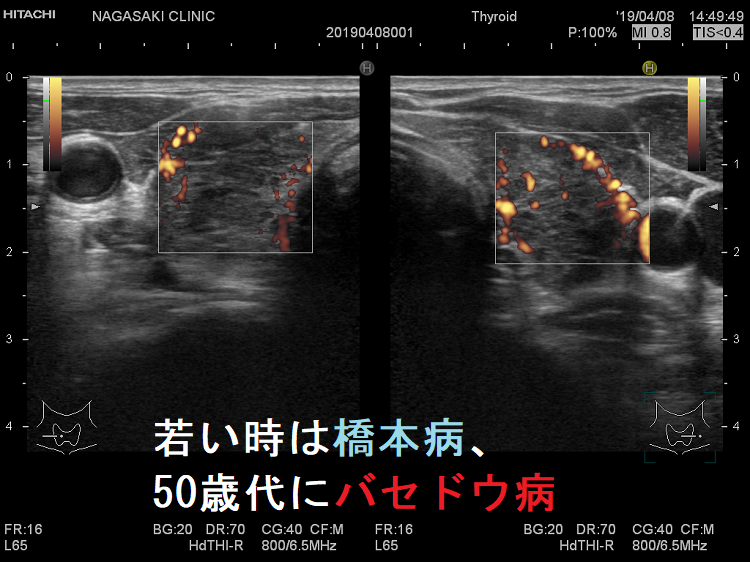

よくあるパターンは「若い時、バセドウ。齢(とし)いって橋本」と言うやつです。(当然、逆もあり)

Th1優位になれば橋本病、Th2優位になればバセドウ病になります。同一人物でもTh1/Th2バランスが変われば、橋本病とバセドウ病が入れ替わるのです。